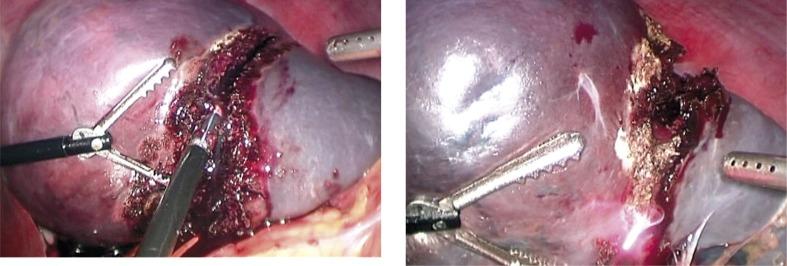

The authors describe a case of sclerosing angiomatoid nodular transformation (SANT) of the spleen treated at the 2(nd) Department of Surgery, Jagiellonian University, Medical College. The patient was a 23-year-old woman. Clinically she presented with 2-year history of recurrent mild fever, diffuse joint pain, abdominal discomfort and iron deficiency anaemia of chronic disease. The laboratory tests revealed a non-characteristic chronic inflammatory response. A splenic solid lesion 9 cm in diameter was found on abdominal computed tomography. The patient underwent uneventful laparoscopic resection of the upper half of the splenic parenchyma. The resected tumour showed characteristic histological and immunophenotypical findings of SANT as previously described in the literature. In long-term follow-up, improvement of preoperative symptoms and abnormalities in the blood tests was documented.

作者描述了一例在雅盖隆大学医学院第二外科治疗的脾脏硬化性血管瘤样结节性转化(SANT)病例。患者为一名23岁女性。临床上,她有2年反复低热、弥漫性关节疼痛、腹部不适和慢性病性缺铁性贫血的病史。实验室检查显示为非特异性慢性炎症反应。腹部计算机断层扫描发现一个直径9厘米的脾脏实性病变。患者接受了脾脏实质上部的腹腔镜切除术,手术过程顺利。切除的肿瘤显示出如先前文献中所描述的SANT的特征性组织学和免疫表型表现。在长期随访中,术前症状和血液检查异常有所改善。